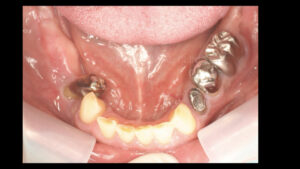

お口の中を見せていただくと左上の奥歯と右下の奥歯が失われています

そして前歯がうまく噛み合っていないので実質噛める歯がほとんどなく

奥歯が壊れるに従って噛み合わせの高さも失われて下の前歯が上の顎に刺さってしまうような状態です

そして奥歯にインプラント治療をしていきますが右下の部分は顎の骨の中の神経付近まで

歯周病によって顎の骨が溶けてしまっているためインプラントができません

また、骨を作る手術も神経が近いため麻痺の可能性を考えるとそれもできません

そこで右下は手前の歯をインプラントで引っ張って周囲の骨ごと引っ張ってその手前に

インプラントを植える治療方法としました